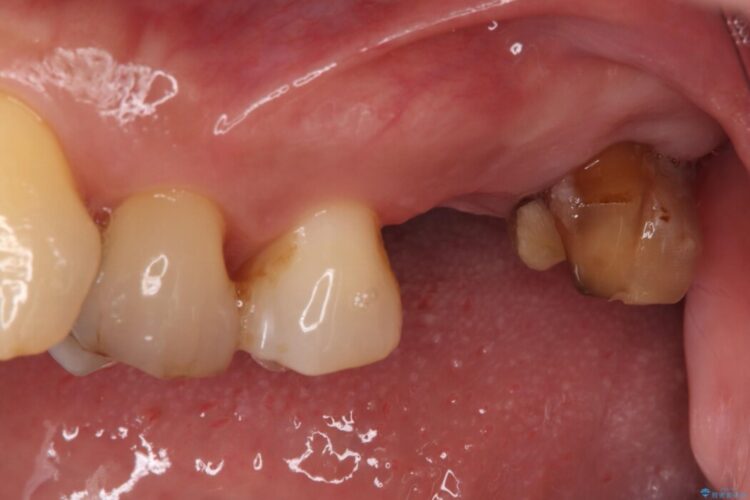

左上奥歯の欠損を、抜歯即時埋入を活用したインプラントで修復しました。

精密な位置決めと効率的な術式により、短期間でしっかり噛める喜びとお口全体の健康なバランスを取り戻すことができました。